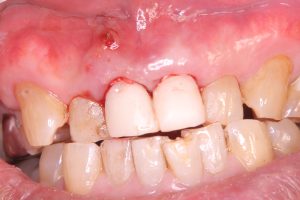

午前にインプラントオペ、ソケットシールド併用

抜歯即時、即時荷重仮歯まで予定

審美エリアだから、歯が無いと困る😅

ISQ80台、ITV70〜80台👍

フラップレス切開無しno incision